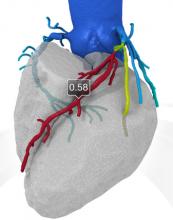

Web Stayman, Ph.D., Johns Hopkins University, presents an overview of research he presented at the 2012 American Association of Physicists in Medicine (AAPM) annual meeting in Charlotte, N.C. It involves an iterative technique for computed tomography (CT) to better contend with implants to improve image-guided surgery or interventions. The technique takes knowledge about the components and integrates it into the reconstruction to eliminate artifacts.